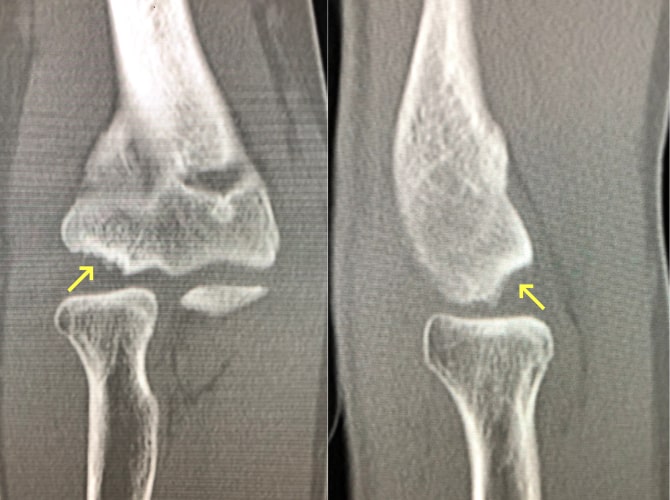

小児上腕骨顆上骨折

上腕骨顆上骨折写真

上腕骨顆上骨折

小児の場合は転倒することで容易に肘周囲の骨折を起こすことがあります。その中でも上腕骨顆上骨折は最も頻度が高く、肘の変形を起こすこともあり注意が必要です。骨折のずれが小さい場合はギプスで固定するのみで骨もつきます。しかし大きくずれてしまっている場合は肘の変形や神経麻痺、血行障害の危険性もあり、手術治療が必要となります。